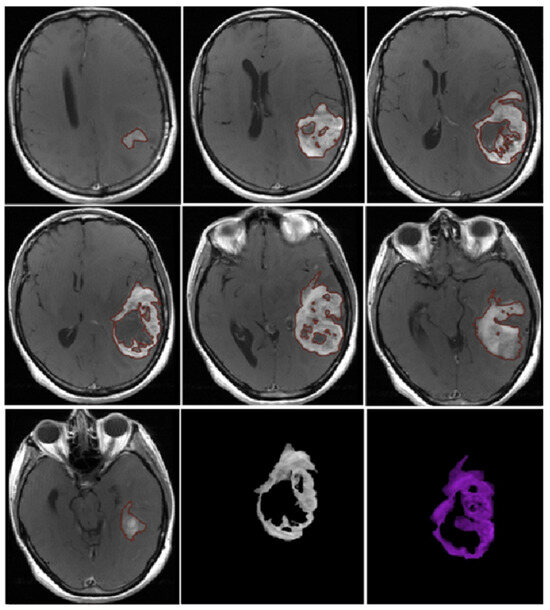

3.2. Quantitative Analysis